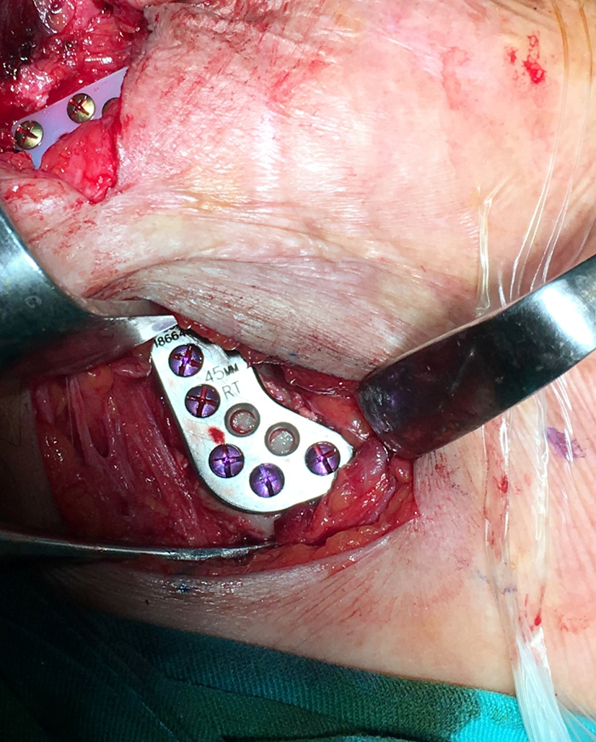

Khoa Phẫu thuật Hàm Mặt sẽ ngày càng hoàn thiện quy trình chăm sóc toàn diện cho bệnh nhân tại khoa với phương châm “Bệnh nhân như người thân”; liên tục cập nhật và áp dụng các tiến bộ khoa học – kỹ thuật, phương pháp điều trị mới vào lâm sàng như máng hướng dẫn phẫu thuật cá nhân hóa, vi phẫu hàm mặt, thay khớp TDH, nội soi lấy sỏi tuyến nước bọt…; chuẩn hóa và nâng cao năng lực khám chữa bệnh cho nhân viên tại khoa: cử bác sĩ, điều dưỡng tham gia các lớp tập huấn ngắn hạn – trung hay dài hạn trong và ngoài nước, đào tạo sau đại học cho toàn thể nhân sự của khoa.